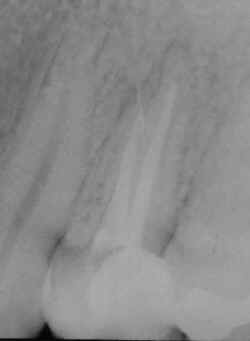

Fratura de instrumento endodôntico metálico com

trepanação apical e conseqüente reação tissular.

Observe

a angulação do instrumento fraturado.

A

certeza de que a imagem corresponde a um instrumento metálico reside na relação entre

suas dimensões e radiopacidade. |